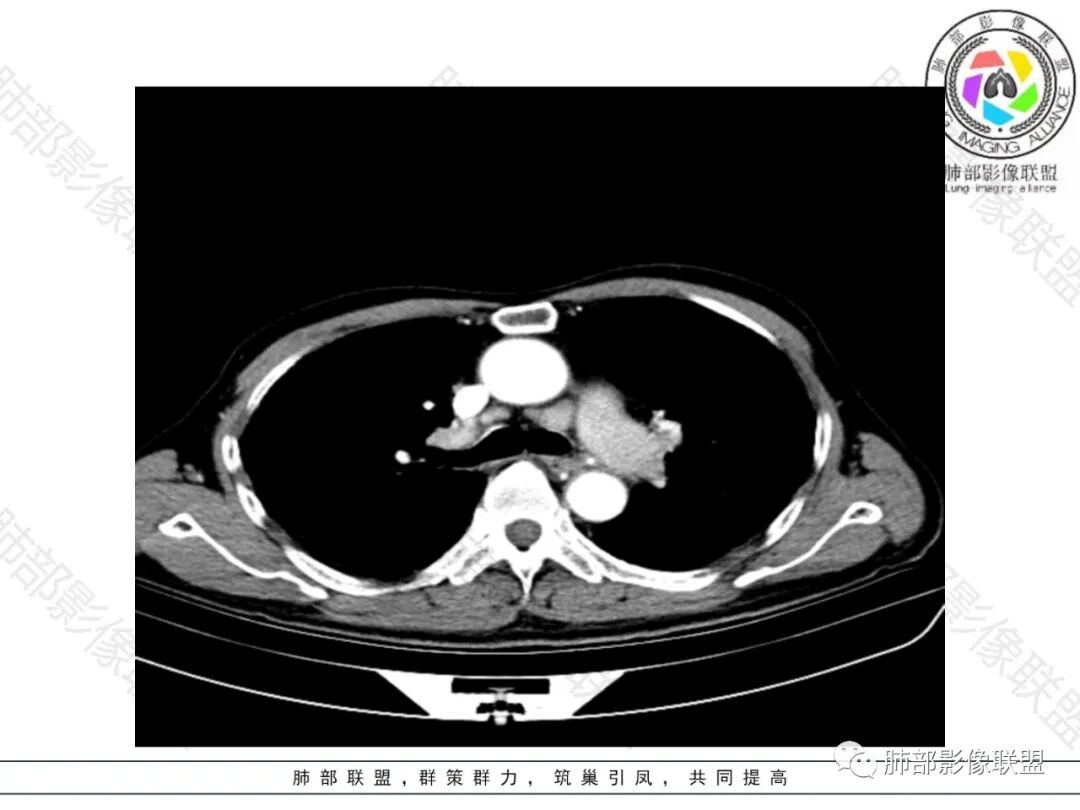

右肺下叶大团块影,斜裂膨隆,内支气管破坏,纵隔窗实质性成份少有强化(假大空),肿瘤CA125、199高,考虑粘液腺Ca右肺门淋巴结及纵隔淋巴结大,右肺下动干起始处充盈缺损(示栓塞或Ca栓;余肺叶弥散网格状改变,间质增厚及纤维化表现!

老年男性的病人。慢性的咳嗽憋喘为主的症状,慢性的病程。临床ca199明显的增高,癌胚抗原升高。白细胞增高提示有肺部感染的。影像学表现两肺弥漫性的网格状改变。而病变又集中在右肺下叶。右肺门见一个大结节的病灶,内部有片状坏死,不均匀的强化,邻近的支气管变窄,周围的肺组织呈大片状的实变影。纵隔淋巴结多个肿大。这样的影像学考虑右侧肺门旁的恶性病变。鳞癌或者粘液性腺癌,伴纵隔淋巴结转移,右肺下叶的癌性淋巴管炎,两肺慢性的间质性肺炎。

老年男性,反复咳嗽咳痰喘憋8年,加重10天,发热半天。白细胞计数明显升高(存在细菌感染可能),CEA、CA19—9升高(肺癌或间质性肺疾病引起可能)。痰培养见肺克。CT;双肺弥漫小叶间质、中轴间质增厚,胸膜下肺气肿,右肺门及右下叶可见实变影,边界模糊,内支气管走形僵硬,部分见蜂窝样改变,增强后实变区可见低密度区(粘液?),叶间裂膨隆,纵隔及右肺门见肿大淋巴结,右肺门淋巴结内见坏死。存在感染,但单纯感染难以解释支气管走行僵硬、实变内的低密度病灶,考虑恶性伴感染,肺炎性肺癌或黏液腺癌。

整个背景是一个肺气肿并间质纤维化,肺气肿以上肺为主(有些地方分不清到底是小叶中心或间隔下肺气肿伴间隔增厚还是蜂窝),左肺下叶正常结构消失,以弥漫网格为主,应该没有多少正常肺功能组织。右肺下叶肺动脉栓塞,再往下几层应该是肿大淋巴结并坏死。右肺下叶的病变考虑粘液性腺癌, 需与感染鉴别(有没有可能是肺梗死呢?)

2.影像表现:肺气肿背景,右肺下叶呈现明显网格影及蜂窝影、枯枝征,边缘膨隆、叶间裂向前方推移。病灶密度不均,前份见不规则片状实性密度区,实性部分轻度强化,边界不清,周边特征掩盖不清。支气管主要分支显示,呈枯枝征。纵隔窗病灶密度偏低,病灶内血管影边缘稍显模糊,未见明显液化坏死区。

右侧肺门淋巴结肿大,中央低密度;纵隔见轻度增大淋巴结。